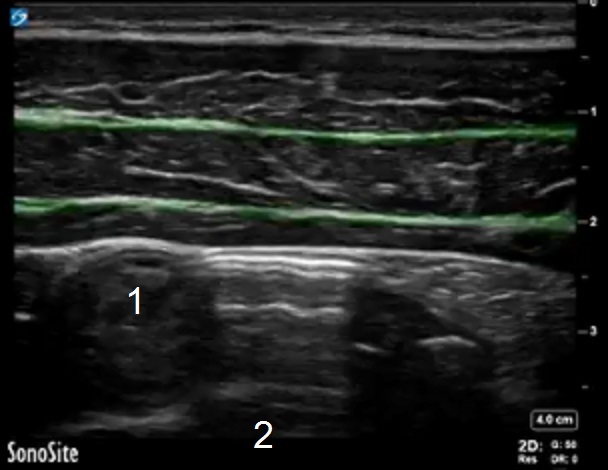

TAP Fascia Highlighted Image

Highlighted Area: Fascia

1. Loop of Bowel in Cross-Section

2. Peritoneal Cavity